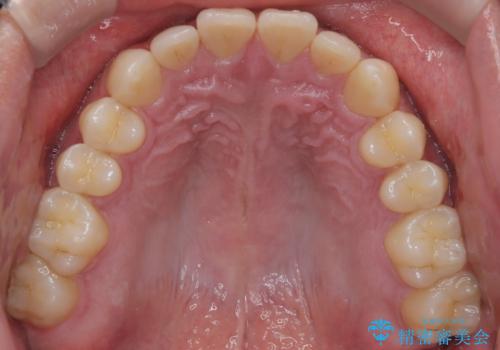

【インビザライン】前歯の隙間を治したい。

- 前歯の隙間を主訴に来院されました。

インビザラインにて治療しました。

ディープバイトも改善でき患者さんも満足されていました。

前歯の隙間だけを閉じる治療を行うだけでは、噛み合わせが悪くなるためディープバイトも改善が必要です。